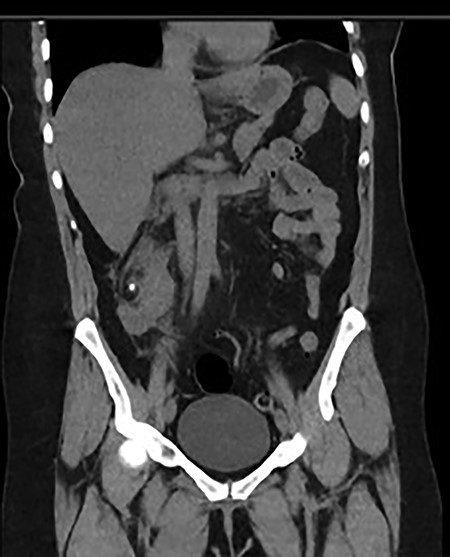

A 60-year-old lady presented to the emergency department with a 1-day history of migratory right lower quadrant pain, diarrhea and associated fevers and rigors. She had a background history of previous diverticulitis and hypertension. On examination, she was shocked with a blood pressure of 86/52, was borderline tachycardiac at 95 bpm, she was tender in the right lower quadrant with guarding and laboratory tests showed acute kidney injury (AKI) with an eGFR of 37 ml/min (previously normal renal function) and a white cell count of 32.9 (109/L). She was referred to the surgical team with a clinical diagnosis of acute appendicitis with an Alvarado score of nine [3]. On further investigation, her urine microscopy showed >500 leucocytes. Because of her age, highly positive urine microscopy (MCS) and AKI, a non-contrast computer tomography (CT) was performed, which showed a malrotated right ectopic kidney with perinephric stranding and a non-obstructing 6 mm calculus in renal pelvis (Fig. 1).

Coronal and transverse CT showing a malrotated right kidney with a non-obstructive calculus and marked perinephric stranding. This ectopic kidney also has an abnormal axis, facing anterolaterally.